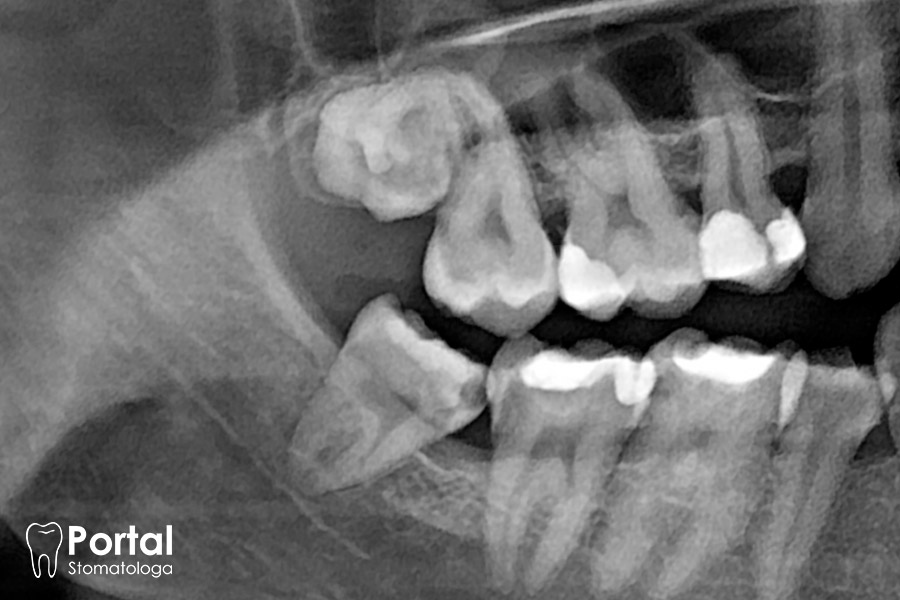

Może stać się to problemem, kiedy dana osoba jest po terapii ortodontycznej. Jednak nie ma obecnie badań potwierdzających, że zęby mądrości powodują znaczne.

Jak już wspominaliśmy, jest grupa stomatologów, która uważa, że zęby mądrości najlepiej prewencyjnie usunąć od razu po ich pojawieniu się. Argument.

Zęby mądrości to ostatnie i najdalej ku tyłowi położone zęby w łuku zębowym. Wyrzynają się u nas jako ostatnie wieku miedzy 18 a 22 rokiem życia, ale przeważnie.